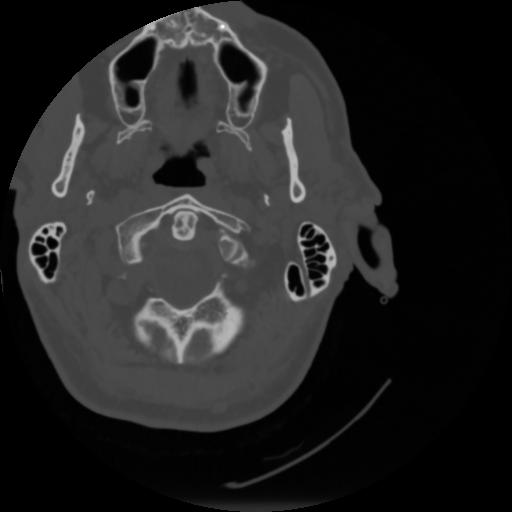

4 CEREBRO,,Vol,0.5,CEREBRO,,